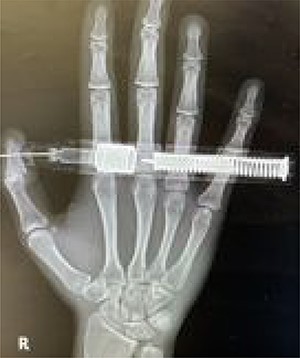

A 19-year-old man presented to the emergency department (ED) with pain and discomfort after accidentally injecting himself with the epinephrine autoinjector while attempting to treat an allergic reaction in a family member (Fig. 1).

On presentation, there was no numbness or paresthesia. The accident occurred 30 min before his arrival to the ED. He accidentally injected 300 mcg of epinephrine (0.3 mg/0.3 ml, and 1:1000) into the volar pulp of his right thumb using the autoinjector. Initially, he experienced moderate pain in the right thumb, which subsided upon arrival to the ED. On examination, a puncture wound was visible on the pulp of the right thumb, distal to the interphalangeal joint. The injector needle was firmly embedded into the volar aspect of the distal phalanx of the right thumb. The digit was warm and pink in color, and the capillary refill was less than 2 s. Sensation was retained in the area distal to the puncture site. The active and passive range of motion of the thumb were intact. His vital signs and oxygen saturation were normal, and there were no signs of impaired peripheral perfusion. A hand radiography did not show a fracture of the distal phalanx of the thumb or the presence of foreign bodies (Fig. 2).

Posteroanterior view of the embedded needle on the right distal phalanx of thumb.